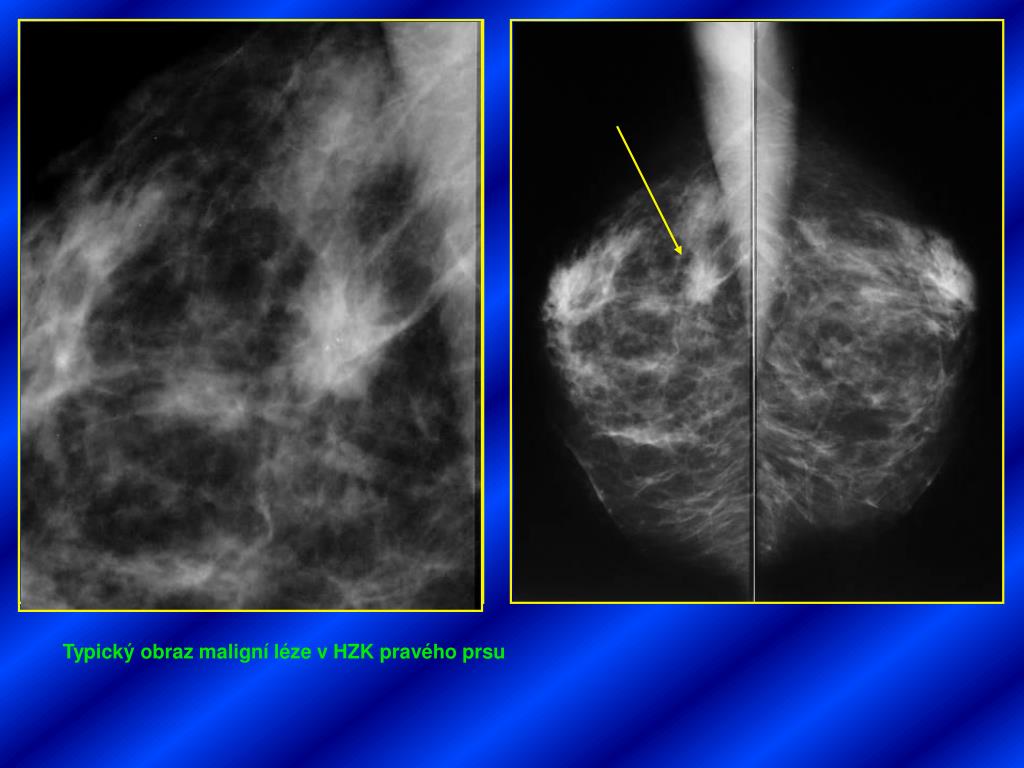

27. Typický obraz maligní léze v HZK pravého prsu

28. Nepravidelný hypoechogenní infiltrát maligní etiologie s reaktivním hyperechogenním lemem V axile jen drobné uzliny benigního vzhledu cca 7mm velké